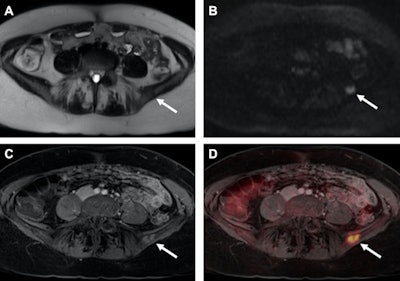

Grueneisen and his fellow researchers have investigated the use of PET/MRI for women's imaging for several years. In a January 2017 study, they found the hybrid modality achieves "superior restaging" with breast cancer patients compared with MRI alone.

The paper followed a 2015 study in which the group found PET/MRI achieved high diagnostic performance for restaging gynecological cancer patients compared with FDG-PET/CT, with only a slightly longer scan time and "markedly reduced" radiation exposure. In 2014, the German researchers concluded that adding diffusion-weighted imaging (DWI) to FDG-PET/MRI to stage women with primary or recurrent pelvic malignancies contributed minimal value and is not worth the additional scan time.